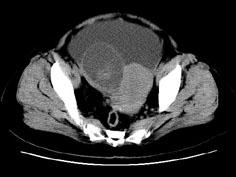

问题 女,27岁,腹胀伴消瘦两个月,CT检查如图所示,应诊断为 ( )

选项 A、卵巢粘液性囊腺瘤 B、卵巢粘液性囊腺癌 C、卵巢浆液性囊腺瘤 D、卵巢浆液性囊腺癌 E、子宫肌瘤

答案 D